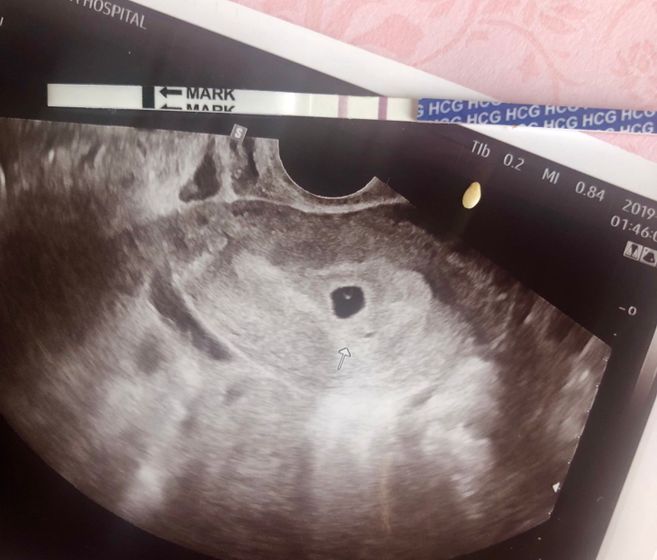

Первая встреча ? размер с кунжутную семечку ❤️ пусть тебе будет тепло, спокойно и уютно в домике ещё 8 месяцев, а потом мы встретимся ?

Да, это ровно в 5 нед делал. Но врач буквально несколько секунд посмотрел что растёт и сразу на капельницу, не замерял ни рассматривал — он противник узи на раннем сроке. Только сказал — очень хорошо! ??